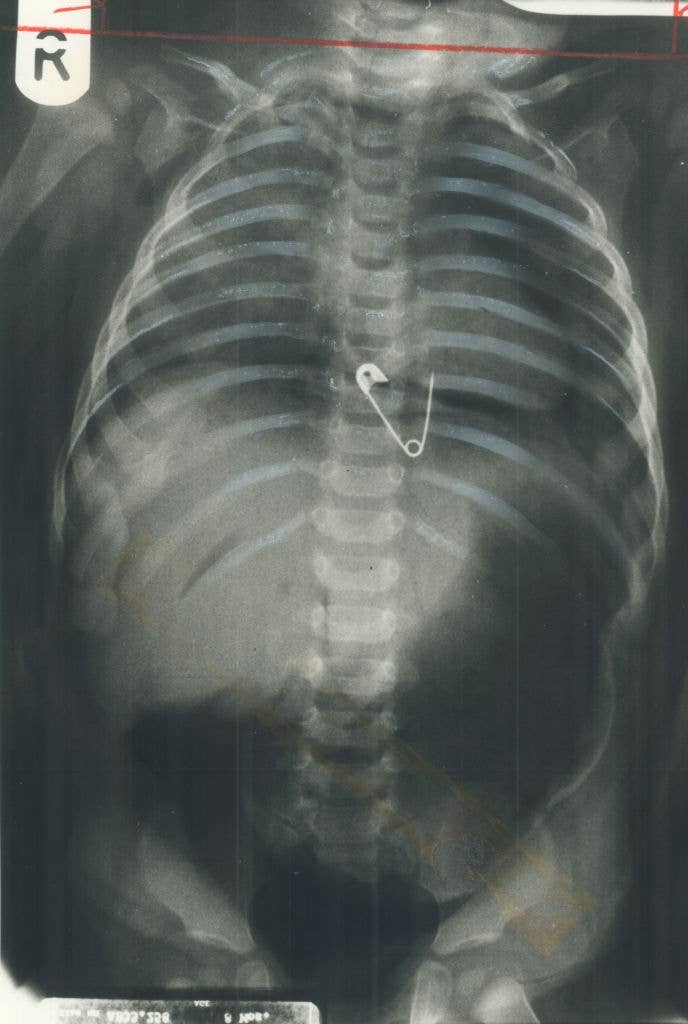

Surgeons, What's The Most Jaw-Dropping Thing You've Seen In The OR?

Be honest, is it actually wilder than Greyβs Anatomy? π